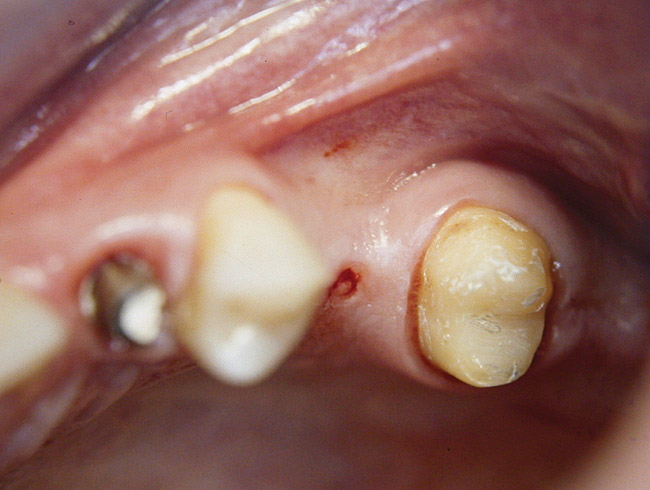

At the time of surgery, local infiltrative anesthesia was administered (lidocaine 2% with epinephrine, 1:100,000). A full-thickness mucoperiosteal flap was raised. The initial osteotomy was performed on midcrestal bone using a rose-headed bur. To prepare the osteotomy site for implant placement, sequential alternating osteotomes with variable conicity were used, drilling 2-mm shorter than the length of the implant to be placed (Figure 3A and Figure 3B). The implants presented initial primary stability (Figure 4), the cover screws were placed, and the implants were submerged for a healing period. The tissue was approximated, and the patient was instructed not to wear any denture or to place pressure on the healing site.

Figure 3a  Alternating osteotomes with variable conicity used to perform the alveolar remodeling in the area of tooth No. 24.

Figure 3a

Figure 3b  Alternating osteotomes with variable conicity used to perform the alveolar remodeling in the area of tooth No. 24.

Figure 3b